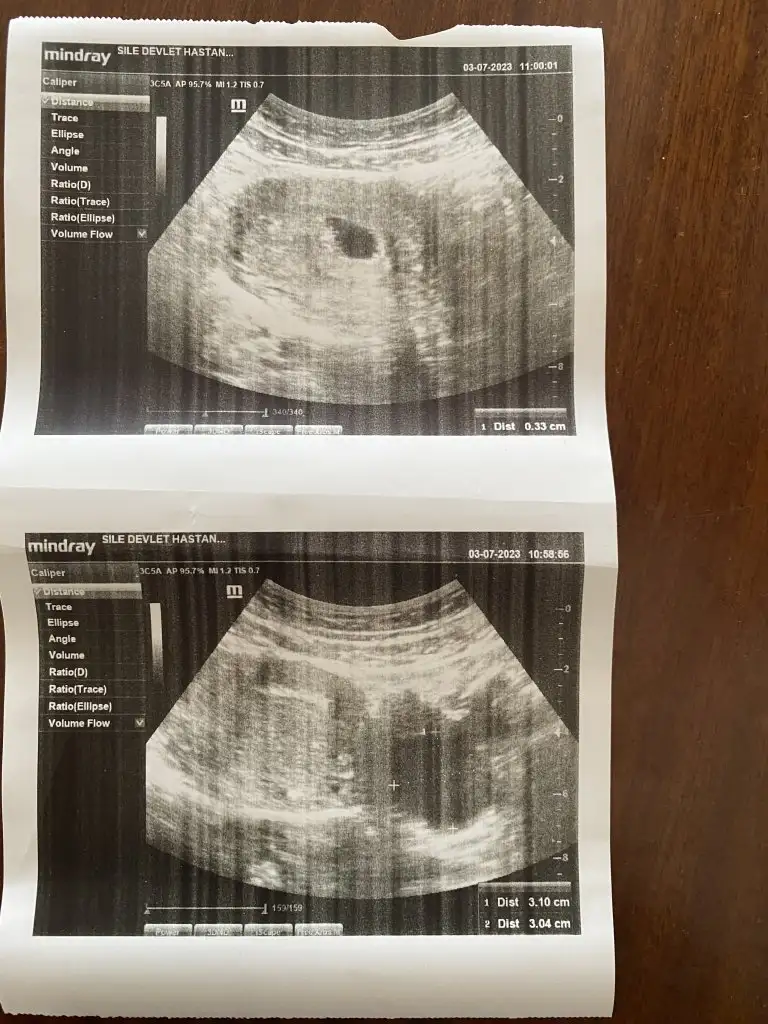

Banada tahminde bulunurmusunuz

• Screenshot_20230808-205807.webp

18 KB · Görüntüleme: 130

• 16914387003257164222940174481301.webp

27,4 KB · Görüntüleme: 117